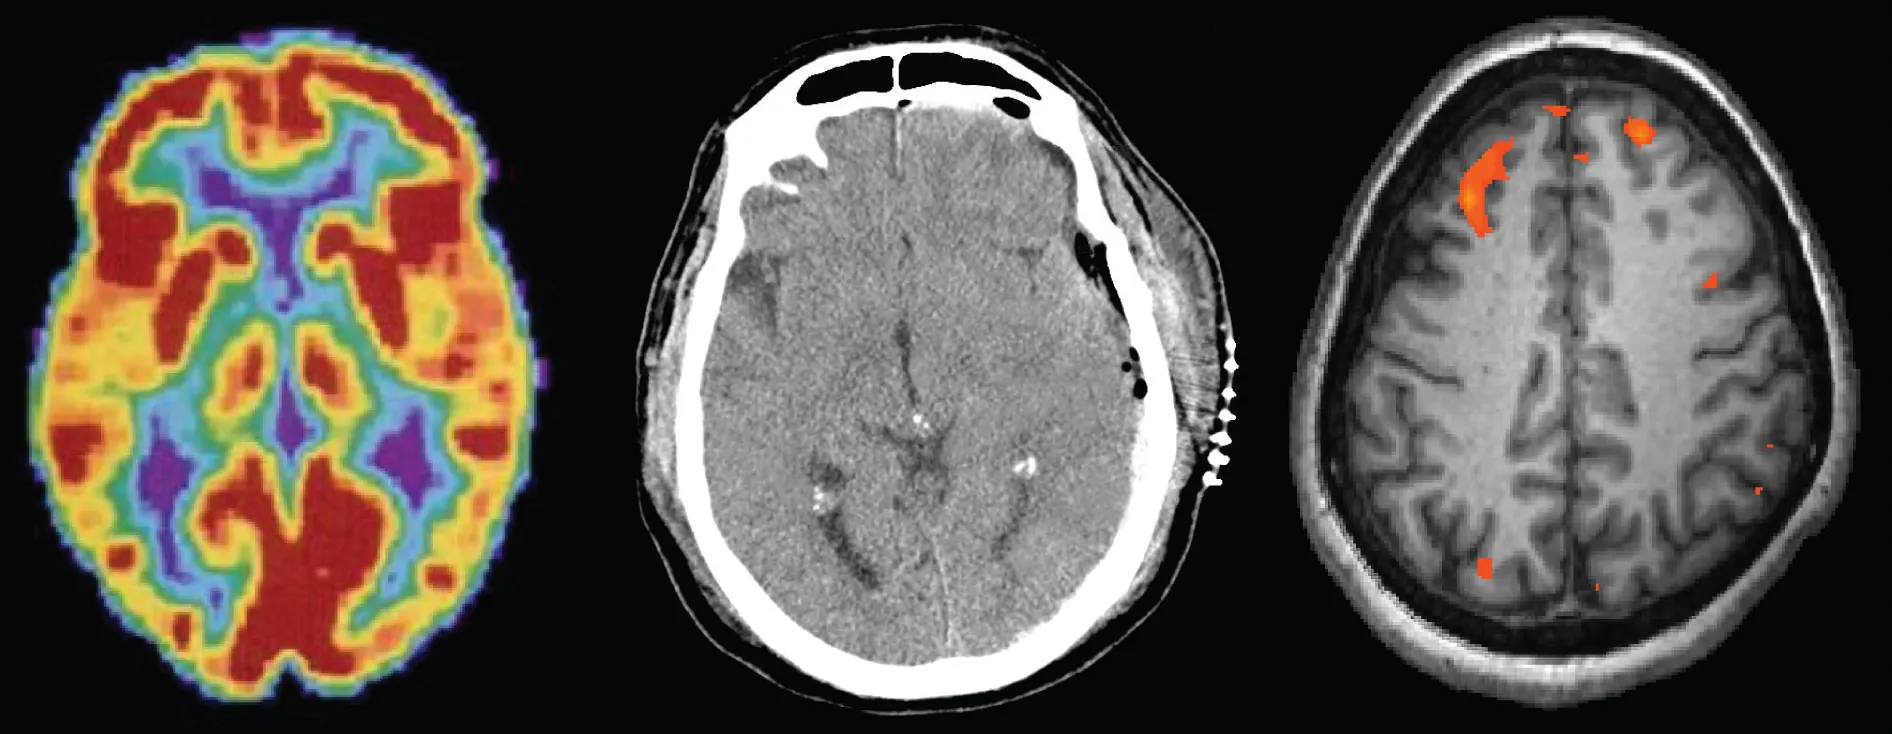

Three brain-imaging scans are shown.

Figure 3.1 Different brain imaging techniques provide scientists with insight into different aspects of how the human brain functions. Left to right, PET scan (positron emission tomography), CT scan (computerized tomography), and fMRI (functional magnetic resonance imaging) are three types of scans. (credit “left”: modification of work by Health and Human Services Department, National Institutes of Health; credit “center": modification of work by "Aceofhearts1968"/Wikimedia Commons; credit “right”: modification of work by Kim J, Matthews NL, Park S.)